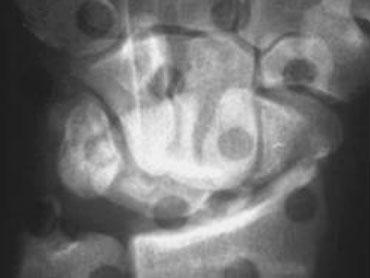

Phân tích:

1. Mất tính song song tại khớp TL (tháp-nguyệt) do xương tháp và xương nguyệt chồng lên nhau.

2. Xương móc và xương nguyệt cũng chồng lên nhau.

3. Có sự song song giữa xương quay, xương nguyệt, cực gần xương thuyền và cực gần xương đầu. Như vậy, các xương này tạo thành một khối thống nhất.

4. Cũng có sự song song giữa xương tháp, xương móc, cực xa xương đầu, xương thang và cực xa xương thuyền.

5. Gãy xương đầu và xương thuyền.

Các dấu hiệu này cho thấy đây là trật khớp quanh nguyệt kèm gãy xương thuyền và xương đầu (transscaphoid, transcapitate perilunate fracture-dislocation).

Bên trái là cùng một ca lâm sàng với đường kẻ chỉ ra đường gãy-trật khớp.

Cùng ca lâm sàng với tư thế chếch và tư thế nghiêng bổ sung, cho thấy tình trạng trật khớp ra phía sau (dorsal dislocation).